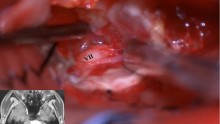

• 大型实性富血运听神经瘤手术复盘

脑肿瘤-神经鞘瘤 其他-自定义

大型实性富血运听神经瘤手术复盘

刘宁

首都医科大学三博脑科医院

昨天18:25 64阅读 0评论 2点赞